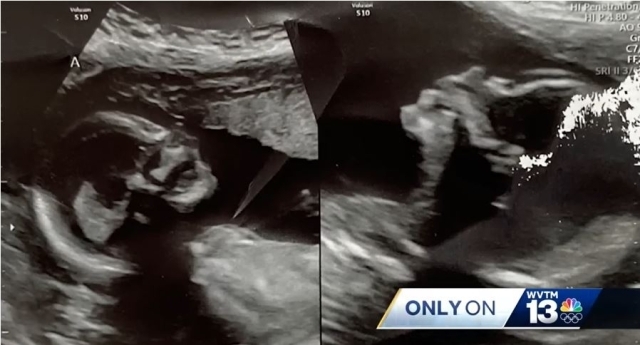

[마이데일리 = 김성호 기자]한 여성이 자궁을 2개 갖고 태어났다. 그런데 이 각각의 자궁에 아이를 임신했다. 그리고 두 태아가 여전히 잘 자라고 있다. ‘쌍둥이 아닌 쌍둥이’는 올 연말, 크리스마스 전후로 태어날 예정이라고 한다.

미국 알라바마주 지역 방송인 WVTM 13은 12일 “키슬리 햇쳐라는 여성이 같은 희귀 사례의 주인공이다”라고 보도했다.

남편 칼렙과의 사이에 키슬리는 이미 7살, 4살, 3살의 아이가 있다. 이번에 태어날 ‘쌍둥이’는 딸이라고 한다.

부인 키슬리는 자신이 두 개의 자궁을 갖고 태어난 것을 이번 봄 처음알았다고 한다. 임신여부를 확인하기위해 병원을 찾았는데 의사가 알려줘서 알았다는 것이다. 그동안 3명을 나을 동안 아무런 이야기가 없었다고 한다.

햇쳐 부부는 의사의 말을 믿지 않았다고 한다. 키슬리는 “의사가 자궁이 두 개가 있고 각각의 자궁에 태아가 있다”는 말을 믿을 수가 없었다. 당연히 이같은 소식을 들은 남편도 믿어지지 않았다.

[자궁을 두 개 갖고 태어난 키슬리 부부. 두 개의 자궁에 모두 태아가 자라고 있어 워낙 희귀한 임신이기에 의학계에서는 출산 예정일인 크리스마스전후를 기대하고 있는 눈치이다. 사진=WVTM 13 캡쳐]